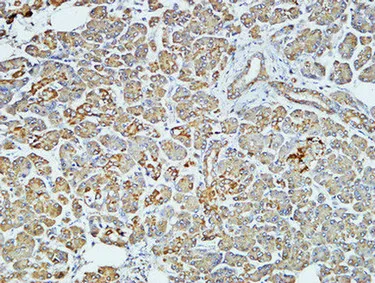

HER2(11H9)Mouse Monoclonal Antibody

Cat: AMM11986

Size1:50μL Price1:$118

Size2:100μL Price2:$220

Size3:200μL Price3:$380

Application:WB,IF-P,IF-F,ICC/IF,IHC-P

Reactivity:Human,Mouse,Rat

Conjugate:Unconjugated

Optional conjugates: Biotin, FITC (free of charge). See other 26 conjugates.

Gene Name:ERBB2